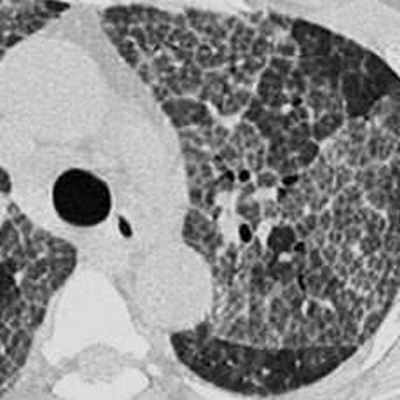

Тяжелая форма микоплазменной пневмонии в виде обширных участков по типу «матового стекла» с практически субтотальным поражением легкого.

Рентгенологическая картина этой пневмонии может быть различной.

При компьютерном томографическом исследовании возможно выявить утолщение легочного интерстиция, участки уплотнения легочной ткани по типу «матового стекла», расположенные перибронхиально или периваскулярно.